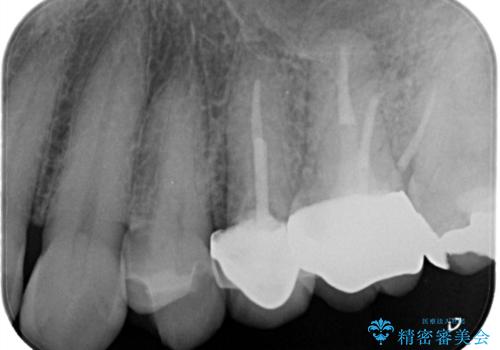

【破折ファイル除去】他院で折れた根管治療の器具をとってほしい

- 他院で折れた根管治療の器具をとってほしいという主訴で来院されました。

マイクロスコープで根管内を観察すると、除去できる状態だったため破折ファイル除去を行いオールセラミッククラウンにて修復治療しております。